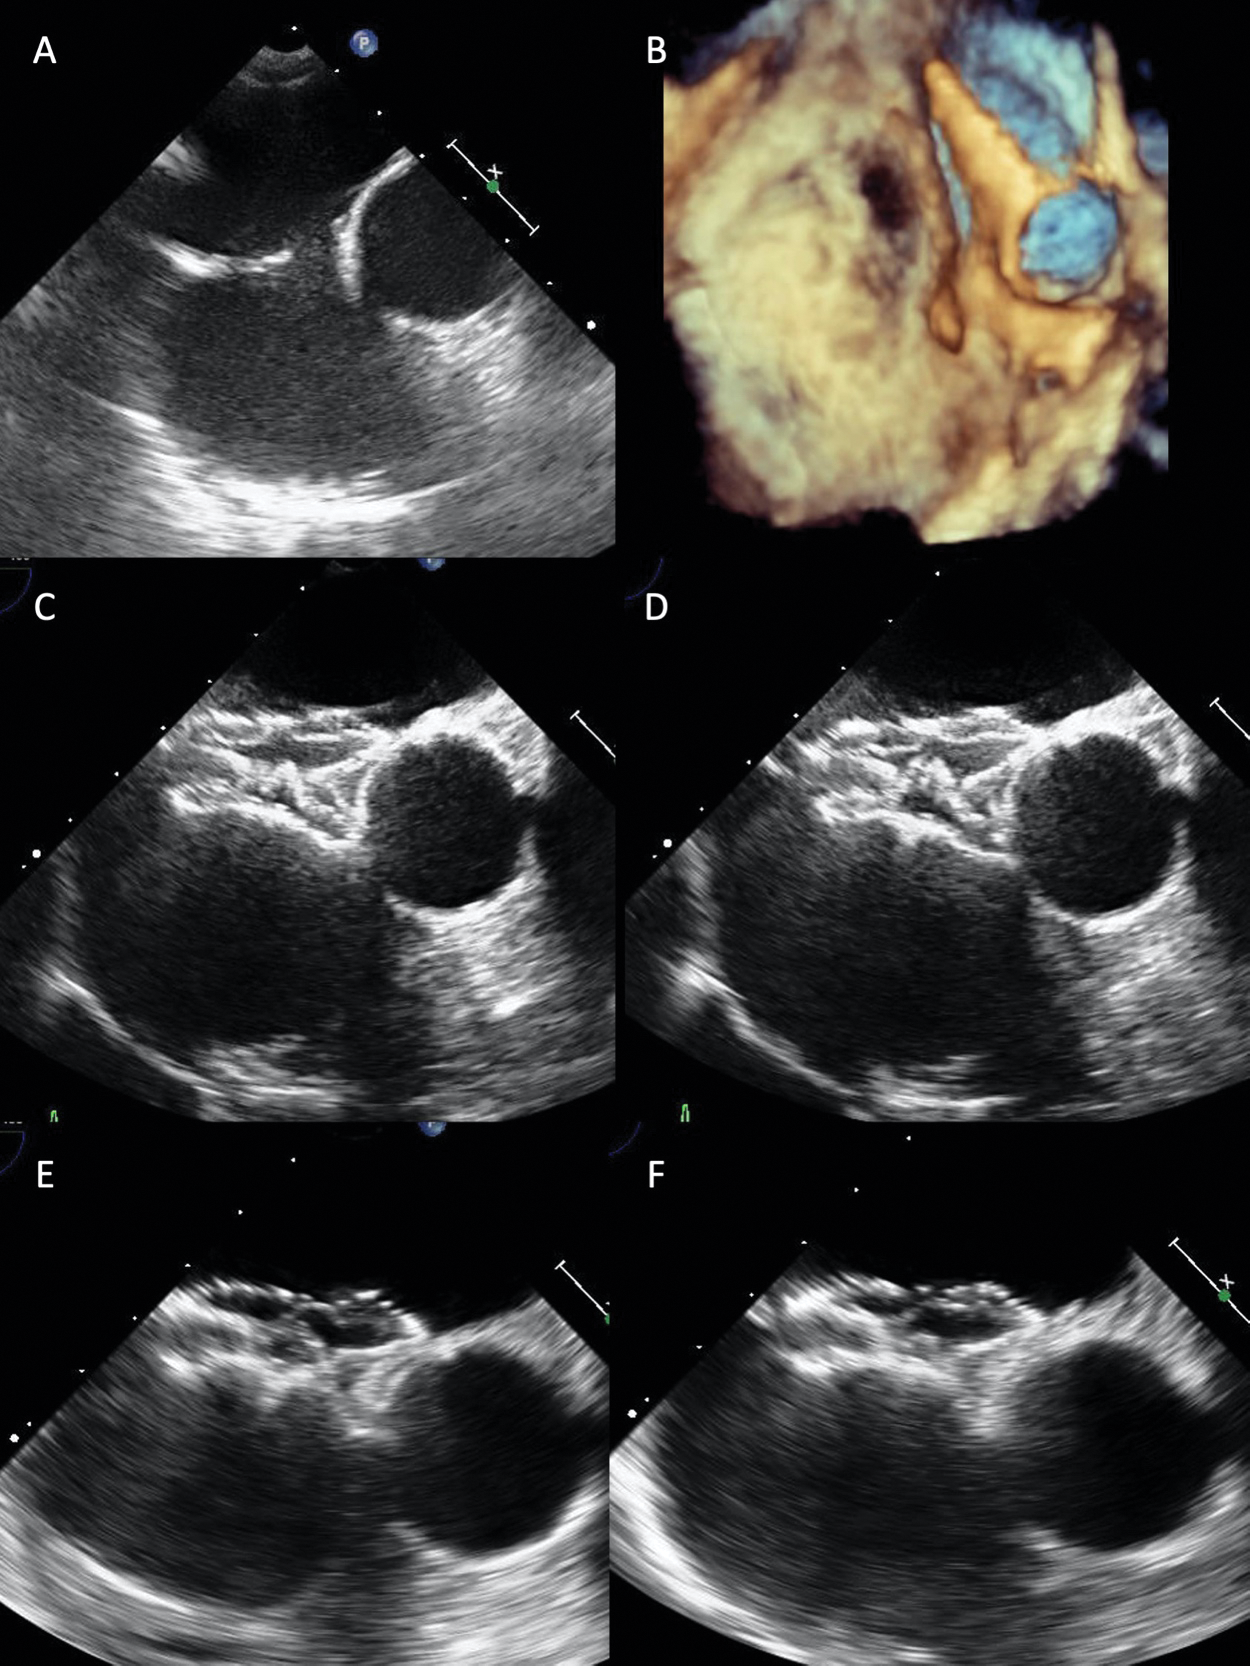

When closing an ASD with a widely malaligned aortic/superior rim, we have to pay attention especially to a patient with a very large Valsalva relative to ASD. Such an ASD requires selection of a much larger device to shape straddling over the aorta. We treated such an ASD patient with malaligned absent aortic and superior rim as follows. For a 9.2 mm × 7.3 mm ASD, we placed a 21 mm FFII around 8 mm larger than the BSD. The device was shaped flared behind the aorta as well as bulky generally, thereby straddling over the aorta. At 6-month-follow-up time, TEE showed that the whole device shape became slightly compact, but the two discs were flared and straddling over the aorta (Fig. 7).

Figure 7: Transesophageal echocardiograms revealing how to close a small ASD relative to the large aorta with a malaligned absent rim. A 21 mm FFII device was placed into the ASD for a 13 mm BSD in a 68-year-old patient who had a 9.2 mm × 5.2 mm diameter small ASD relative to the large aorta with widely malaligned absent aortic and superior rim (A, B). Immediately after placement (C, the farthest phase of the device from the aorta; D, the nearest phase of the device), two discs flare and the whole device shape becomes bulky, thus straddling over the aorta without pressure to the aortic wall. At 6 months after placement (E, farthest phase; F, nearest phase), the whole device shape becomes slightly compact, but the two discs become more flared over the aorta. Hence, the disc edges do not appear to be pressing the aortic wall